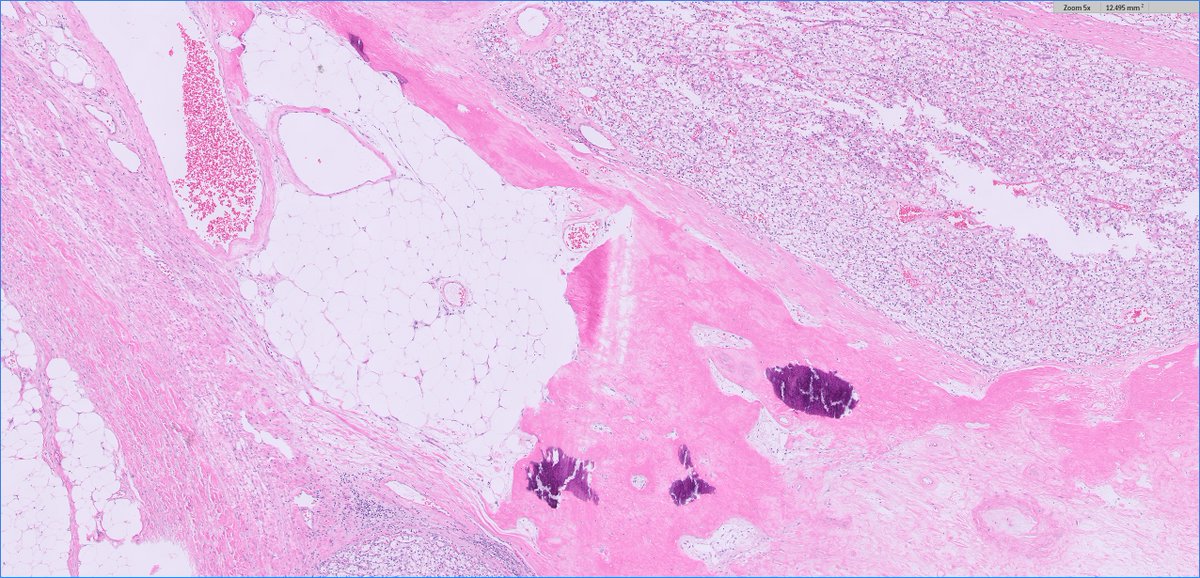

70s F, partial nephrectomy. What is your diagnosis? Gross photo in the chat. #PathTwitter

@MGBpathology @MGHPathology @PathDocBoston